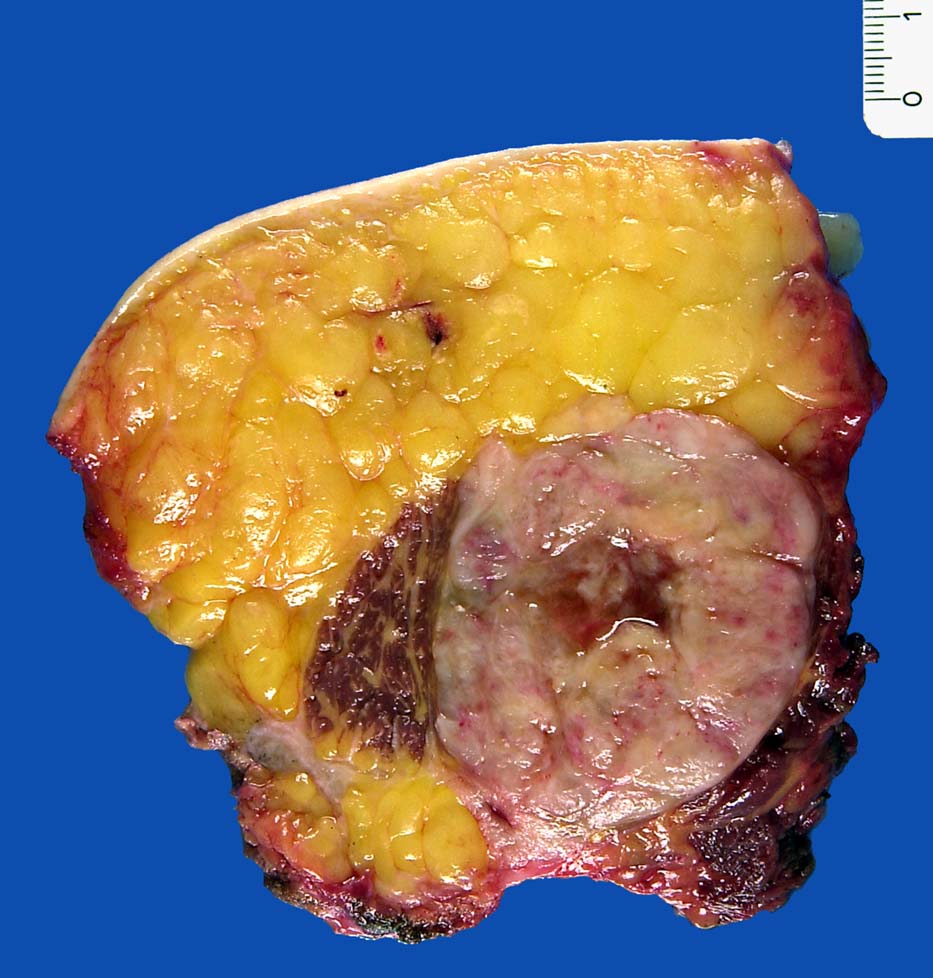

PathoPic – image database / PathoPic ID 9161 - Pleomorphes Liposarkom

Pleomorphes Liposarkom

Haut- und Weichteilexzisat mit randständigen Skelettmuskulaturanteilen (Gluteus maximus). Auf Schnitt erkennt man einen direkt innerhalb des Musculus gluteus maximus gelegenen 9.5cm im Durchmesser messenden weisslichen, fasrigen, zentral nekrotischen Tumor.

Pleomorphes Liposkarkom

Pleomorphes Liposarkom-Rezidiv; St. n. Radiotherapie.